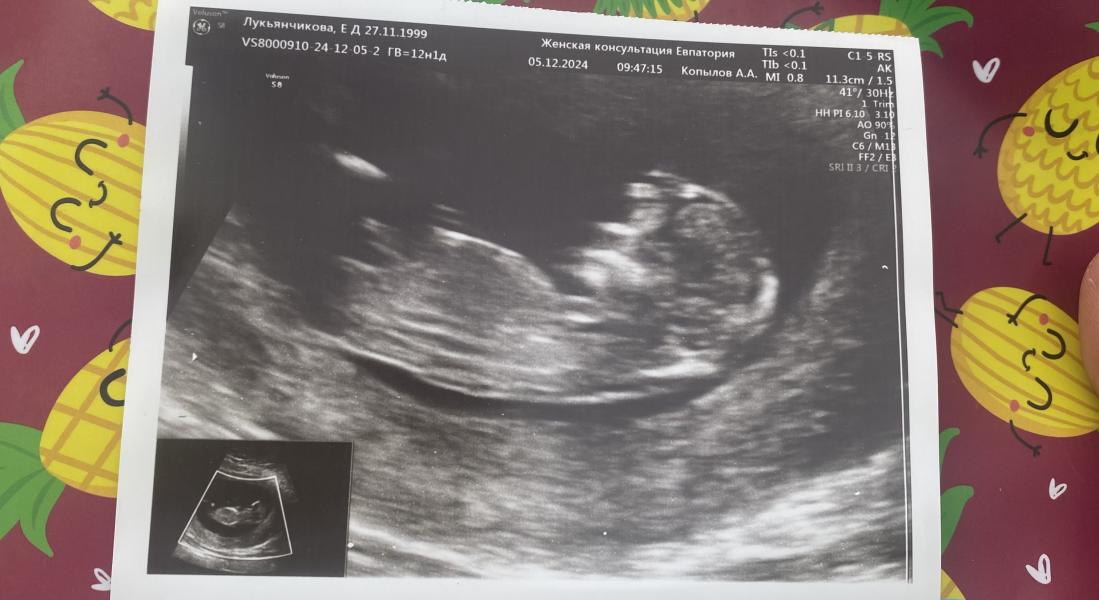

Была на первом скрининге)

Малыш шилопоп,с первого раза не могли посмотреть все хорошо,отправили на кровь,как сказал узист,чтоб немного напугать и понервничать (что больно кровь сдавать) и малыш перевернулся,вернулась- говорит все сработало)

Посмотрели,все отлично,уже прям человек😃

Фото мое,узист сказал,что сейчас конечно же не понятно,но в сторону мальчика склоняется почему -то

@luckyanchikovaekaterina, половой бугорок расположен горизонтально

Мне кажется девочка

Если это ваше фото то кажись девчонка